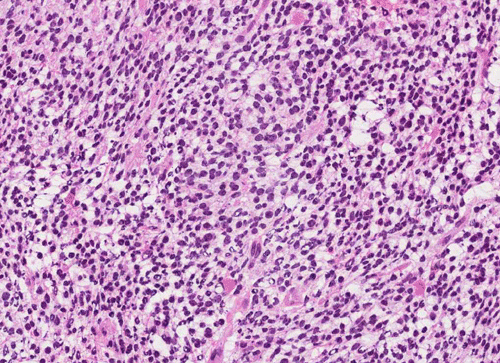

Squash

Pathology of the Case: The tumor is composed of neoplastic small blue cells on the cytologic preparation (Pancel C and D) with only minimal amount of cytoplasm. On frozen section (Panel E and F), the tumor cells are packed in solid sheets without specific pattern of arrangement. On permanent sections, the tumor again is composed of solid sheets of small blue cell tumors with rather monotonous nuclei (Panel G and H). In some areas, there is some small neuropil islands (Panel I). No distinct perivascular coronary arrangement is noted.  (Panel J). There is a moderate labeling index on Ki67 (Panel K). The tumor cells are strongly positive for neurofilament proteins (Panel L). Some large stellate, cells positive for glial fibrillary acidic protein (GFAP) are also present and these cells may represent reactive astrocytes (Panel M).